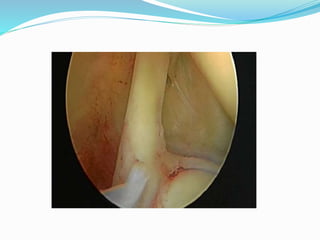

El documento trata sobre la anatomía y la funcionalidad del complejo articular del hombro, enfocándose en espacios quirúrgicos específicos en la región posterior. Se presenta información relevante sobre la cintura escapular y su relación con el hombro. El análisis realizado por el Dr. Luis Francisco Chávez Flor abarca aspectos clave para la comprensión de procedimientos quirúrgicos en esta área.